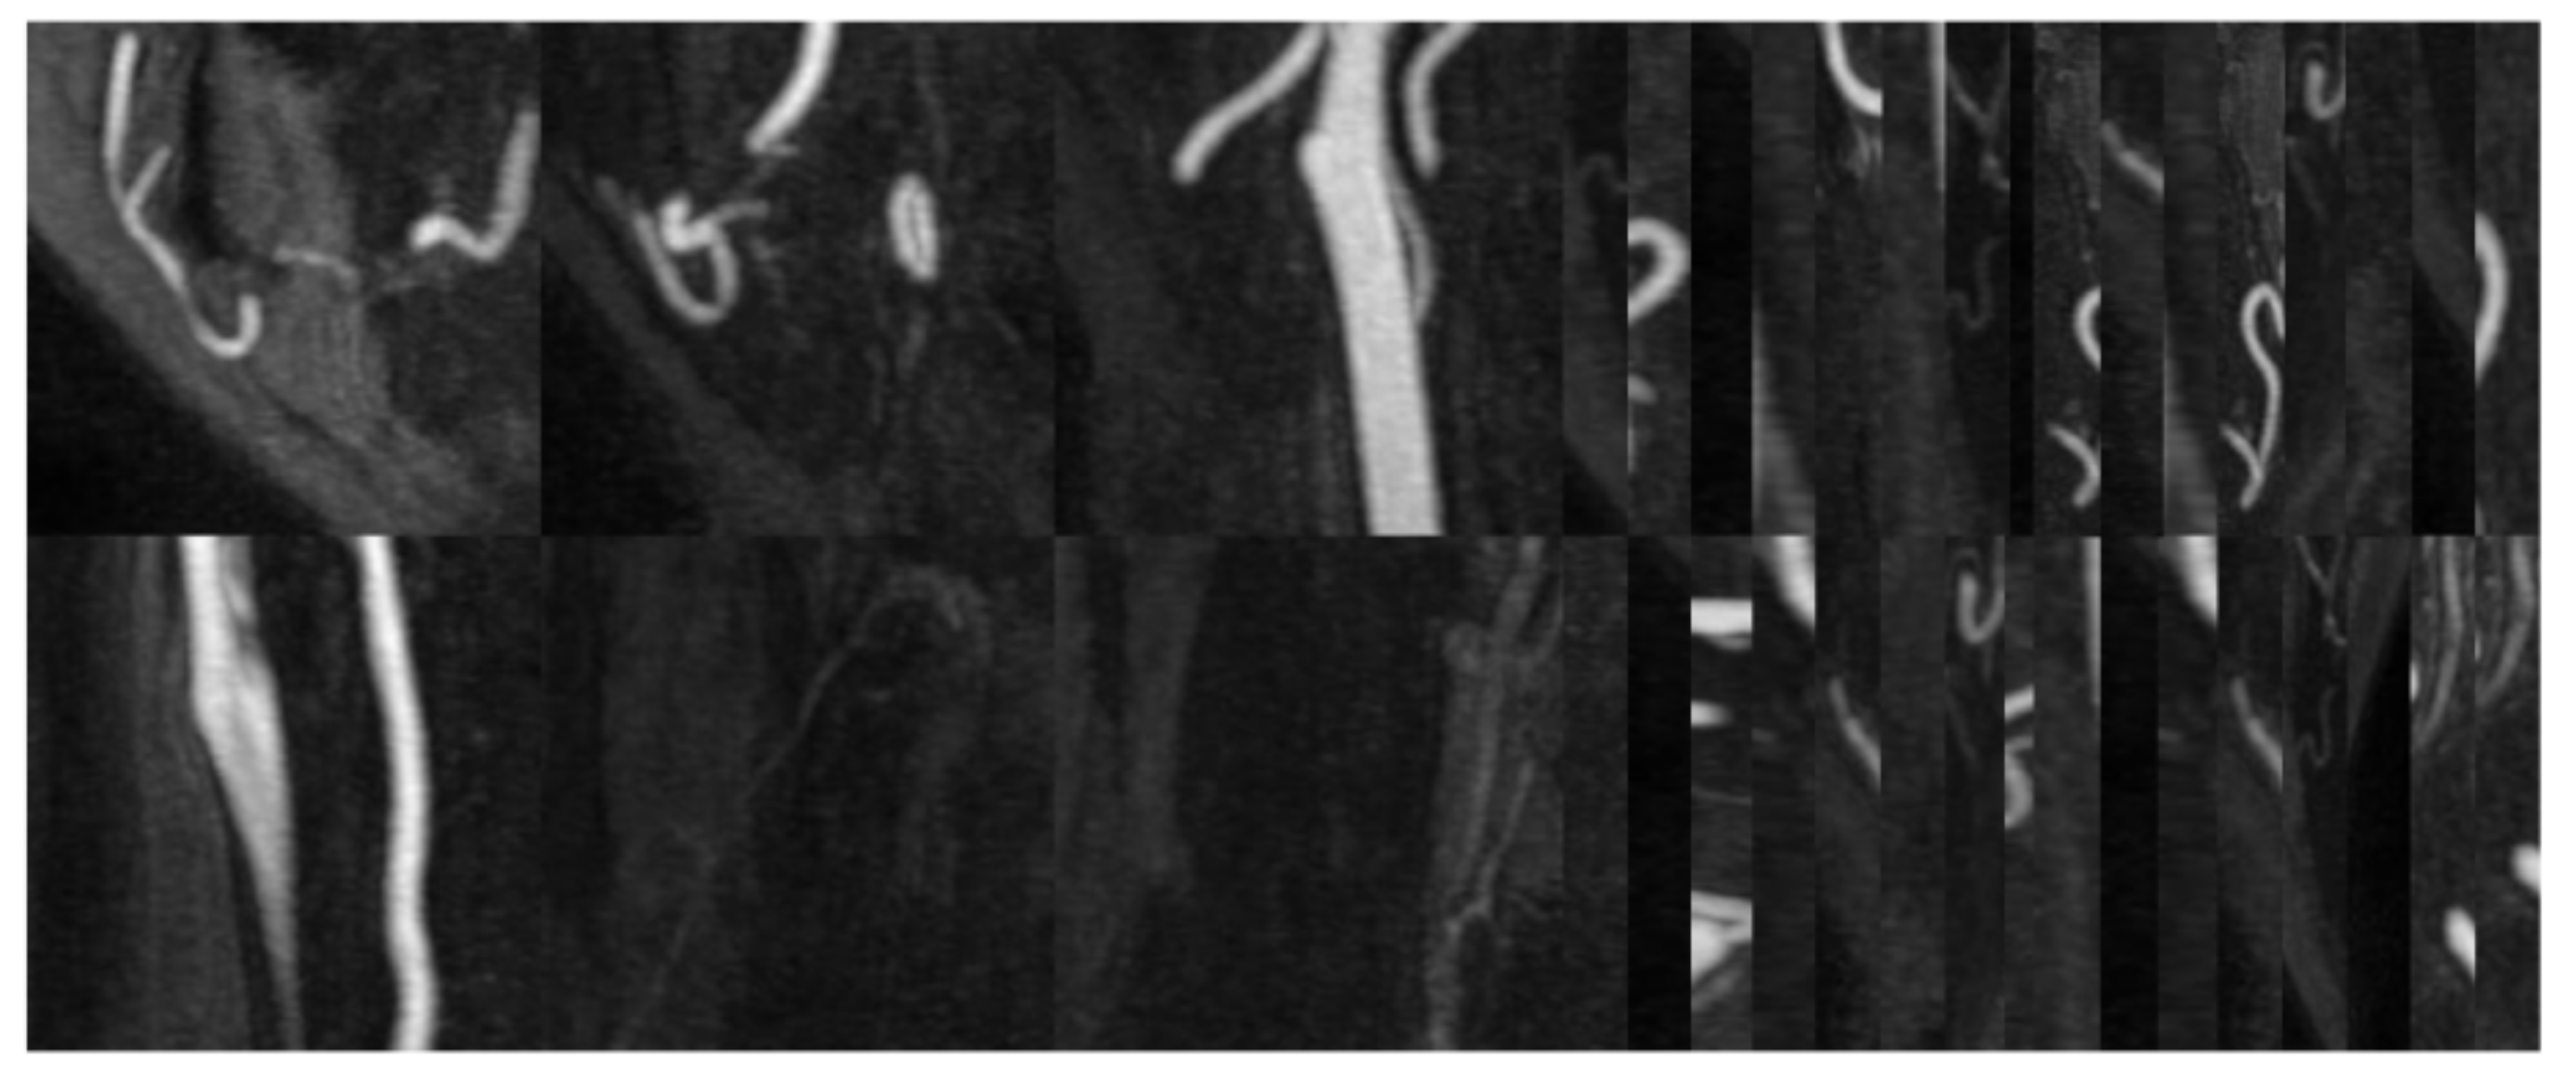

3.4. Ablation Study